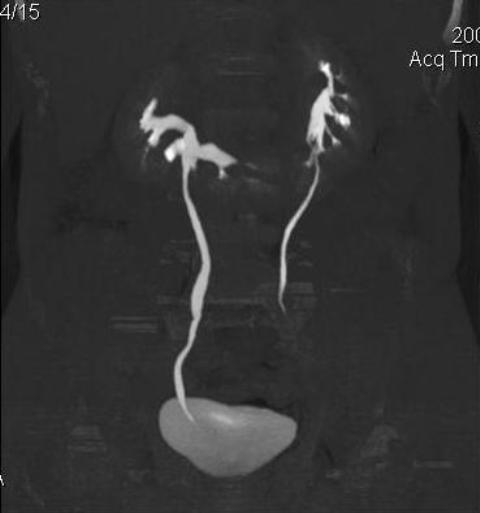

КТ Почек- подкова и уретеролитиаз

Ну ладно, раз никто больше не хочет, то отвечу свою версию - аномалия развития - подковообразная почка (horseshoe kidney).

Да красивая подковообразная почка - встречала раз 6-7.

Не вызывает сомнений. Картинка замечательная. Должно быть хорошо видно и на УЗИ.

Почечная колика; на последнем аксиальном скане чётко виден мелкий (2 мм) камень в устье правого мочеточника.

Для невладеющего КТ,очень четка видна аномалия на 3-4х снимках.А вот на 4-м скане в проксим.сегменте цистоида тоже есть гиперденсное точечное образование-не камень случайно?